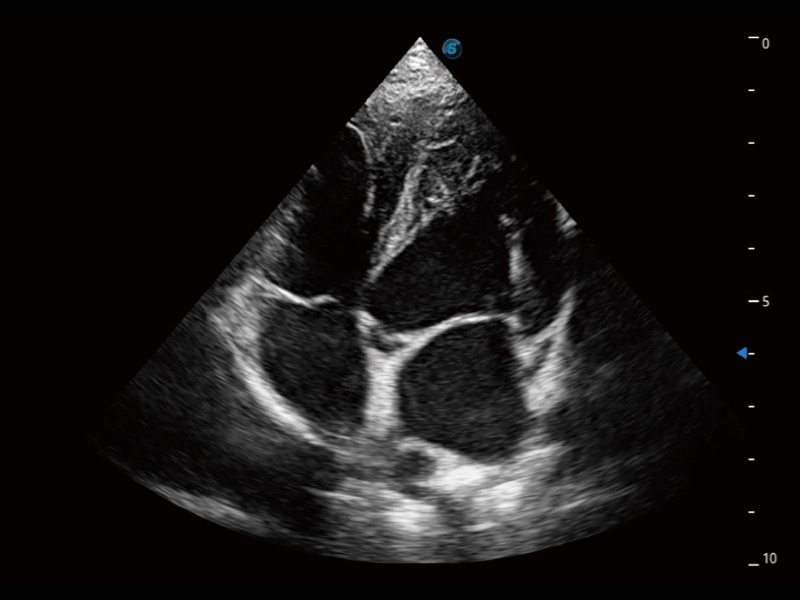

大型犬、马科、农场动物及大型异宠动物

当心脏测量结果超出正常范围时,可实时预警提示动物医生,减少疾病漏诊概率。